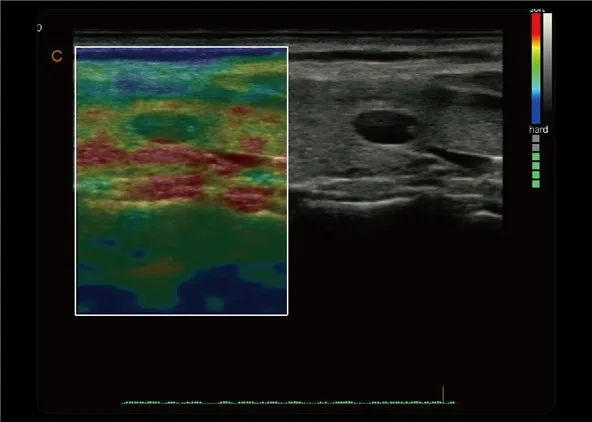

Elastografía cuantitativa

● Mostrar la elasticidad de diferentes tejidos en diferentes colores

● Proporcionar más información clínica, especialmente para tumores de mama, tiroides, hígado y próstata.

● La medición de la relación de deformación proporciona cuantitativamente la relación entre la deformación media de la región seleccionada y la de la región de tejido normal cercana.

● Disponible en transductores versátiles.